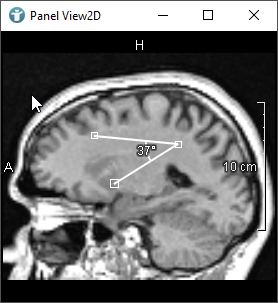

As mentioned, when creating CSOs, you can do this interactively by using an editor.

The following images show editors available in MeVisLab for drawing CSOs: